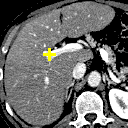

Figure 6: Example comparison among VTN ADDD + inv (c/d), Elastix (e/f), ANTs (g/h) and VoxelMorph-2 (i/j). (a) sections of the fixed image (a CT liver scan); (b) sections of the moving image (another CT liver scan); (c/e/g/i) sections of the warped images and landmark distances; (d/f/h/j) sections of the warped segmentations (white for the fixed and semi-transparent red for the warped) and segmentation IoUs. Crosses indicate the projection of landmarks (L2, L3 and L4 from top to bottom), yellow (lighter) for one in the fixed image, red (darker) for the corresponding one in the moving/warped images. Best viewed in color.

Figure 6 compares different methods listed in Table II, where three landmarks are selected and the sections of the volumes at the height of each landmark in the fixed image are rendered. This means the red crosses (landmarks in the moving and warped images) indicate the projections of the landmarks onto those planes. It should be noted that though the sections of the warped segmentations seem to be less overlapping with those of the fixed one, the Segmentation IoU is computed for the volume and not the sections. It might well be the case that the overlap is not so satisfactory when viewed from those planes yet is better when viewed as a volume. Similarly, overlapping red and yellow crosses do not necessarily imply overlapping fixed and warped landmarks as they might deviate along z𝑧z-axis.